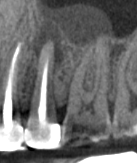

CBCT Scans provide a 3D dental image, while traditional X-rays are only a 2-dimensional picture of the mouth. This means that with traditional X-rays alone, it is very difficult to diagnose non-painful lesions like dental abscesses that are within the jaw bone.

Here are some examples of photos of bone lesions

Patient “A ”Xray of a root canal tooth #14 CBCT Scan of same tooth #14, notice the lesion on the bone at the tip of the left root Notice root canal #13 on xrays CBCT Scan on same tooth #13, there is a lesion at the tip of the root causing sinus membrane inflammation. Patient “C” xray tooth #14 Patient “C” CBCT Scan tooth #14, bone lesion affects both roots. Upland Lighthouse Dentistry, a renowned family dentist in Upland, offers cone beam CBCT scan technology for comprehensive dental care. Our expert dentist utilize this advanced 3D imaging technique to obtain precise details of dental structures, soft tissues, and nerve paths, enhancing our diagnostic accuracy and treatment planning. Contact Upland Lighthouse Dentistry today!